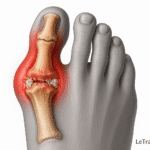

Déformations du pied

Les malpositions comme l’hallux valgus déplacent l’appui du pied et créent des zones de frottement. Ces déséquilibres favorisent l’apparition d’une bursite, notamment sur l’avant-pied ou le talon.

Bursite inter-métatarsienne et chaussage étroit

Cette bursite survient entre les os du pied, souvent à cause de chaussures trop serrées comprimant l’avant-pied. Elle provoque une douleur localisée entre les orteils et une gêne lors de la marche.

Un diagnostic précoce de l’hallux valgus ou d’autres malpositions permet une correction par orthèses, limitant ainsi les frottements et les risques de bursite.

Oui. L’hallux valgus et d’autres déformations créent des zones de frottement anormales, augmentant fortement le risque de bursite.